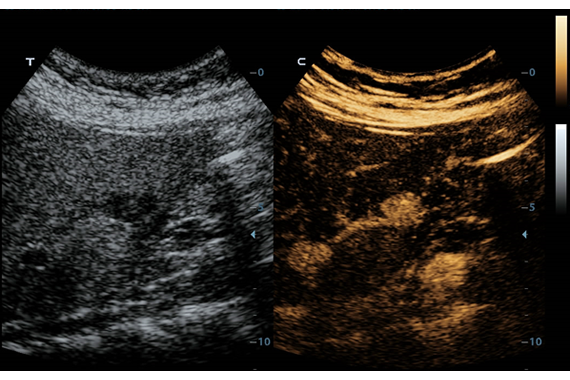

X-Insight – это отличное решение для определения новых возможностей.

–°–æ–≤–º–µ—Å—Ç–Ω–æ —Å —Å–æ–≤—Ä–µ–º–µ–Ω–Ω—ã–º–∏ —É–ª—å—Ç—Ä–∞–∑–≤—É–∫–æ–≤—ã–º–∏ —Ç–µ—Ö–Ω–æ–ª–æ–≥–∏—è–º–∏ –Ω–æ–≤–æ–µ —Ä–µ—à–µ–Ω–∏–µ –æ—Ç Mindray –ø—Ä–µ–æ–±—Ä–∞–∑—É–µ—Ç –∞–∫—Ç—É–∞–ª—å–Ω—ã–µ –∑–∞–¥–∞—á–∏ –∫–ª–∏–µ–Ω—Ç–æ–≤ –≤ –∫–ª–∏–Ω–∏—á–µ—Å–∫–∏–µ –ø–æ—Ç—Ä–µ–±–Ω–æ—Å—Ç–∏. –ü–æ—Å—Ç–æ—è–Ω–Ω–æ —Ä–∞–∑–≤–∏–≤–∞—è—Å—å, —ç—Ç–∞ —Å–∏—Å—Ç–µ–º–∞ —Å–æ—á–µ—Ç–∞–µ—Ç –≤ —Å–µ–±–µ —Å—Ç—Ä–µ–º–ª–µ–Ω–∏–µ –∫ –Ω–µ–æ–≥—Ä–∞–Ω–∏—á–µ–Ω–Ω—ã–º –≤–æ–∑–º–æ–∂–Ω–æ—Å—Ç—è–º –∏ –∂–µ–ª–∞–Ω–∏–µ –∑–∞–≥–ª—è–Ω—É—Ç—å –≤ –±—É–¥—É—â–µ–µ.

–ú–Ω–æ–≥–æ—Ñ—É–Ω–∫—Ü–∏–æ–Ω–∞–ª—å–Ω–∞—è —Å–∏—Å—Ç–µ–º–∞ DC-60 Exp —Å X-Insight –ø—Ä–µ–¥—Å—Ç–∞–≤–ª—è–µ—Ç —Å–æ–±–æ–π –∫–æ–º–ø–ª–µ–∫—Å–Ω–æ–µ —Ä–µ—à–µ–Ω–∏–µ, –∫–æ—Ç–æ—Ä–æ–µ –ø–æ–º–æ–≥–∞–µ—Ç —É–ø—Ä–∞–≤–ª—è—Ç—å –ø–æ–≤—Å–µ–¥–Ω–µ–≤–Ω–æ–π –∫–ª–∏–Ω–∏—á–µ—Å–∫–æ–π –ø—Ä–∞–∫—Ç–∏–∫–æ–π —Å –ª–µ–≥–∫–æ—Å—Ç—å—é –∏ —É–≤–µ—Ä–µ–Ω–Ω–æ—Å—Ç—å—é.